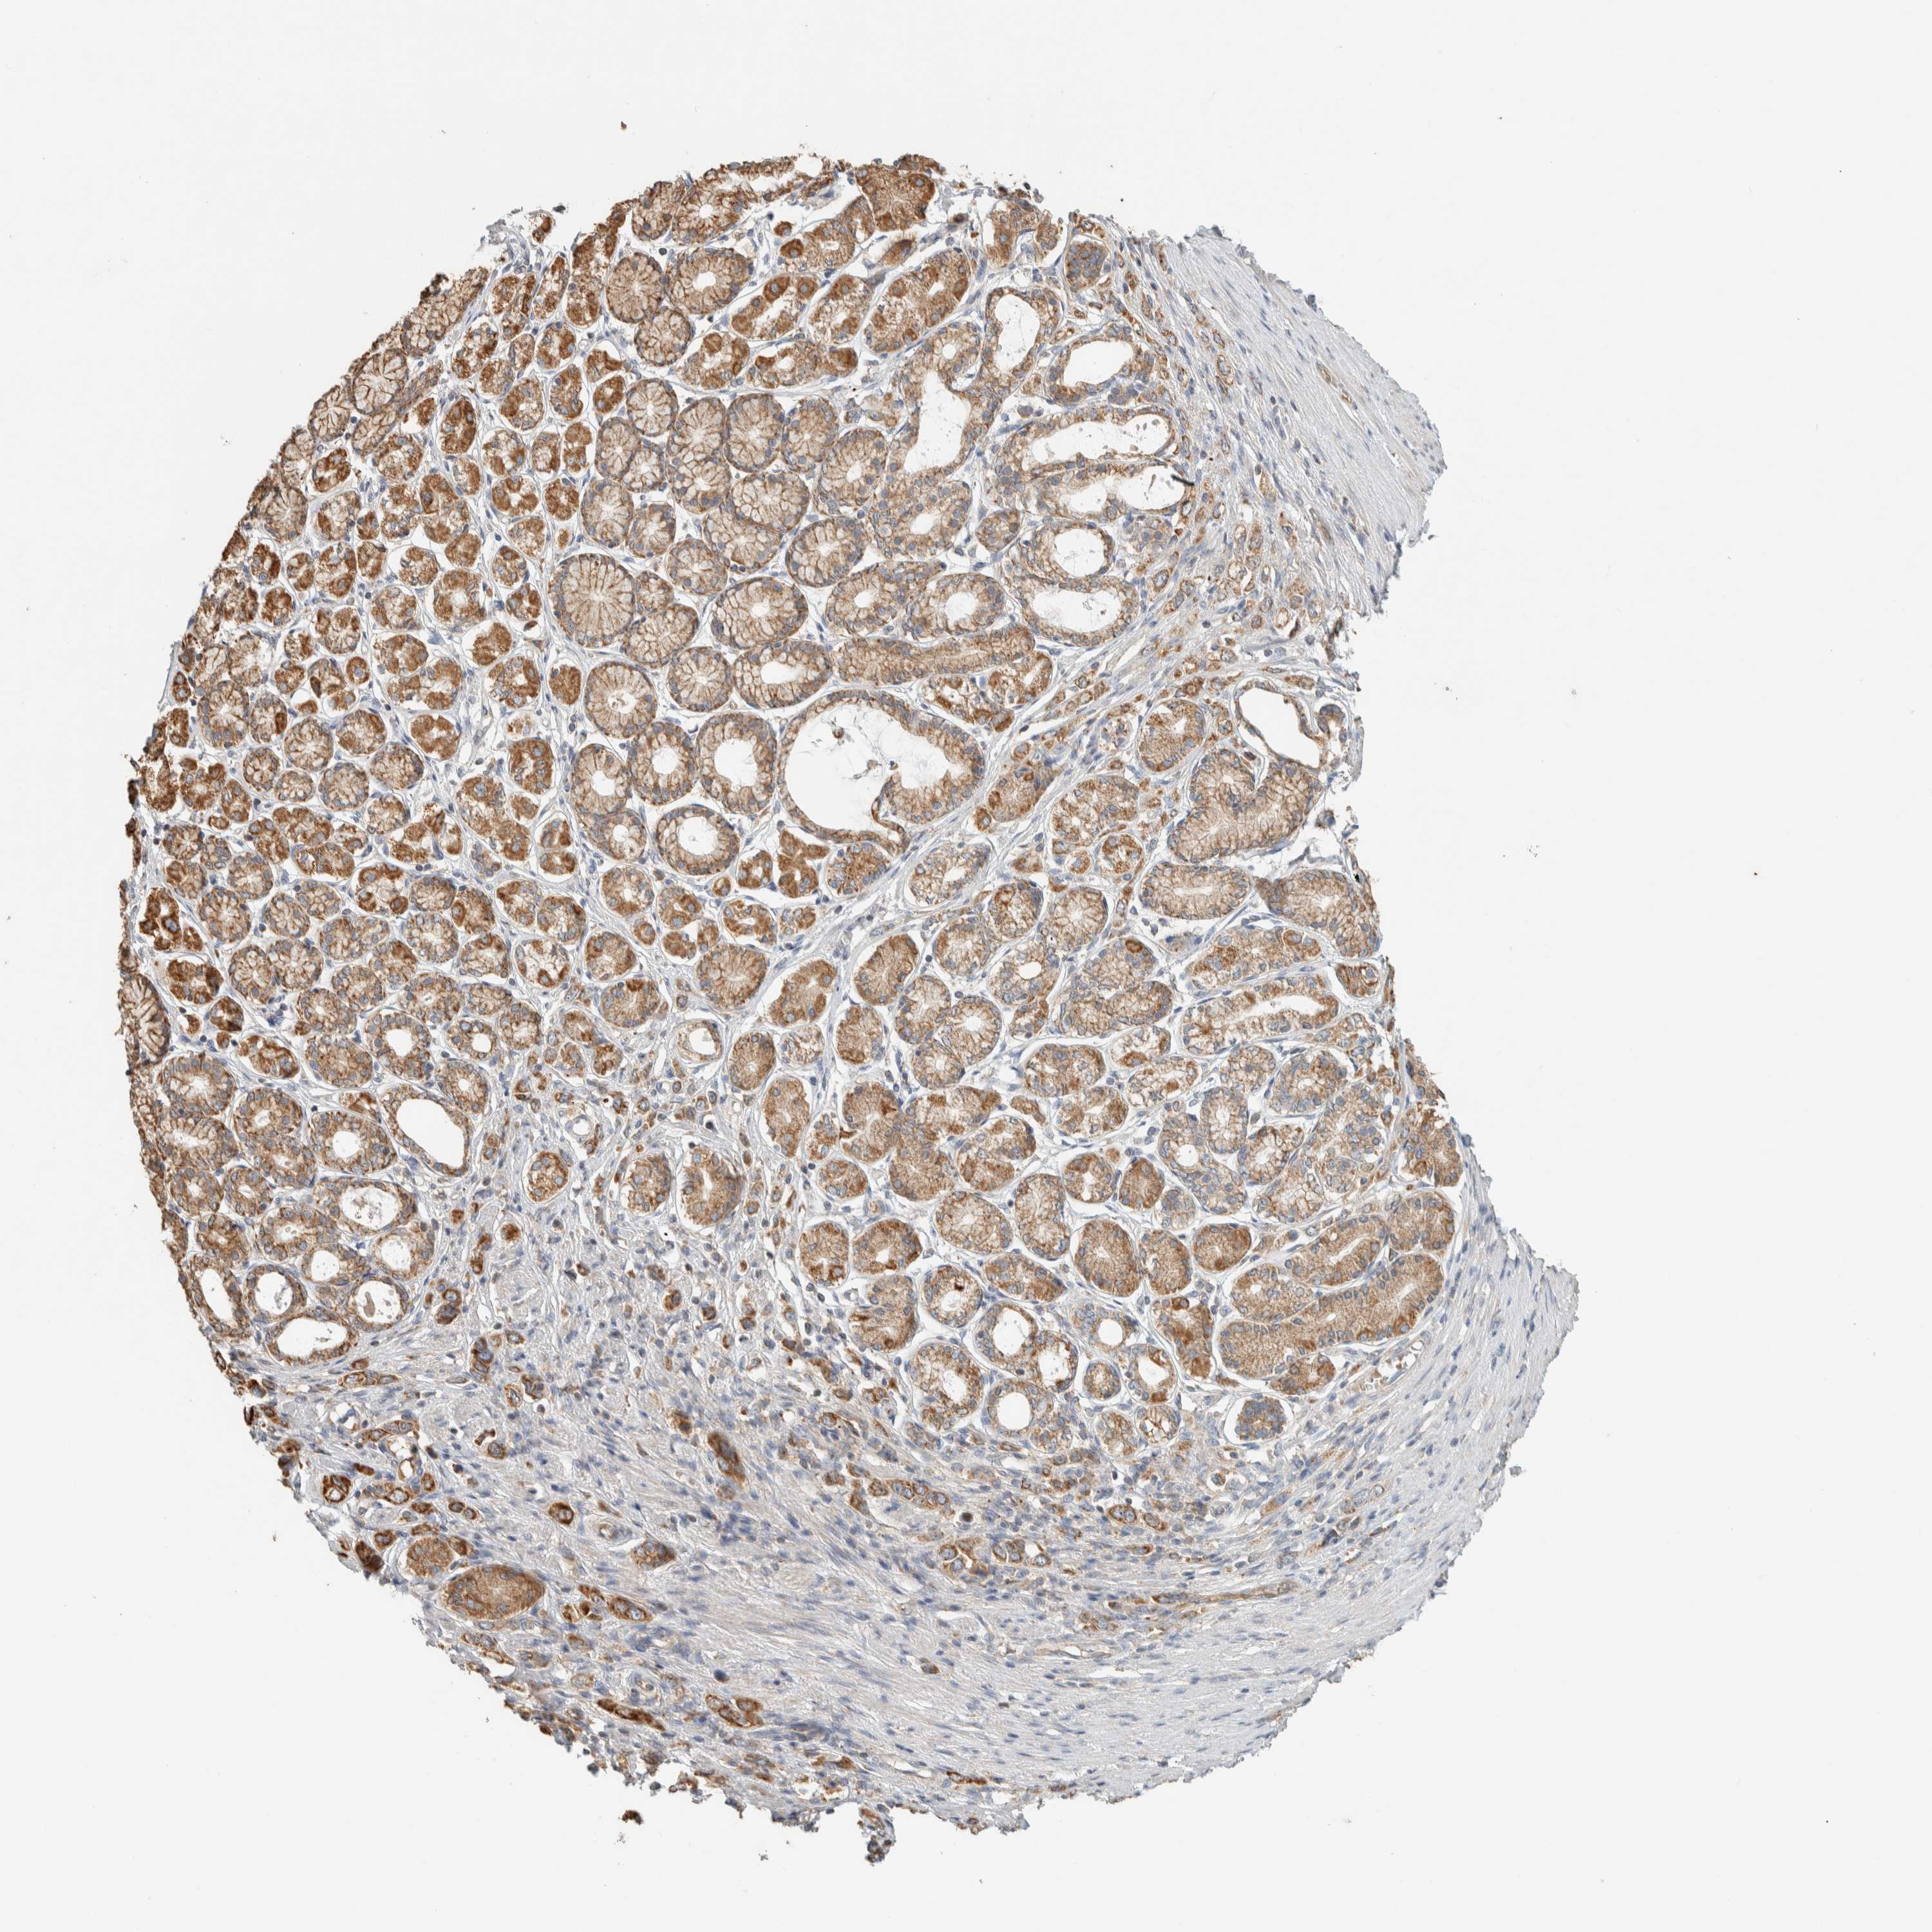

STOMACH CANCER - Protein expressioni

A mouse-over function shows sample information and annotation data. Click on an image to view it in a full screen mode. Samples can be filtered based on level of antibody staining by selecting one or several of the following categories: high, medium, low and not detected. The assay and annotation is described here.

Note that samples used for immunohistochemistry by the Human Protein Atlas do not correspond to samples in the TCGA dataset.

Antibody stainingi

Antibody staining in the annotated cell types in the current human tissue is reported as not detected, low, medium, or high, based on conventional immunohistochemistry profiling in selected tissues. This score is based on the combination of the staining intensity and fraction of stained cells.

Each image is clickable and will lead to virtual microscopy that enables deeper exploration of all samples and also displays staining intensity scores, fraction scores and subcellular localization as well as patient and tissue information for each sample.

Antibody HPA023904

Antibody HPA024010

Antibody HPA025960

Antibody CAB017037

Staining

High

Medium

Low

Not detected

Intensity

Strong

Moderate

Weak

Negative

Quantity

>75%

75%-25%

<25%

None

Location

Nuclear

Cytoplasmic/membranous

Cytoplasmic/membranous,nuclear

Adenocarcinoma, NOS